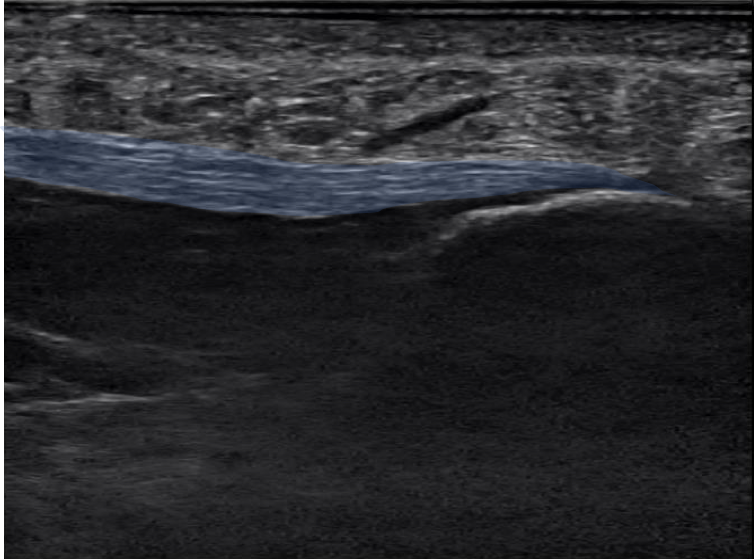

例)足底腱膜炎

足底腱膜の変性(腫れ)の評価(矢頭)

当グループでは超音波診断装置を用いて注射を行っています。

レントゲンやMRI、超音波診断装置でどこが病因なのかを探りその部位に注射を行います。